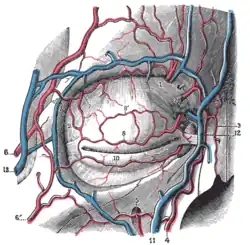

Visão frontal dos vasos sanguíneos dos próximos às sobrancelhas.

Visão frontal dos vasos sanguíneos dos próximos às sobrancelhas.